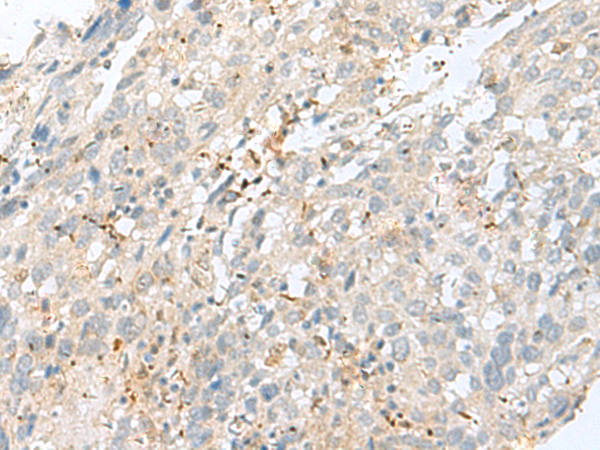

分类: 科研抗体货号: P02868别名: TPMTD应用: IHC反应种属: Human